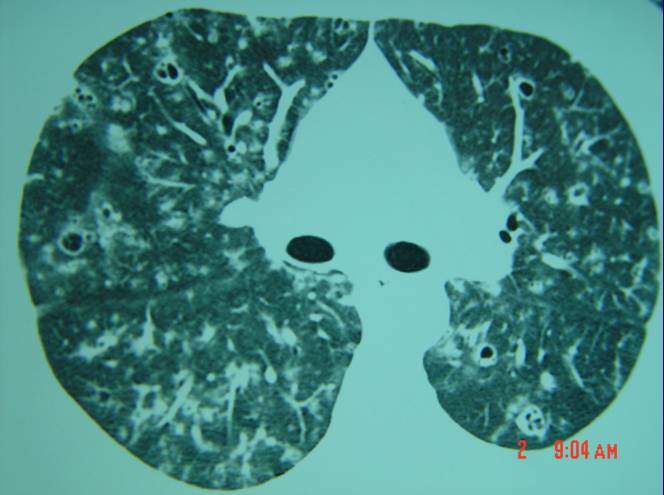

图27:淋巴细胞性间质性肺炎(lip)